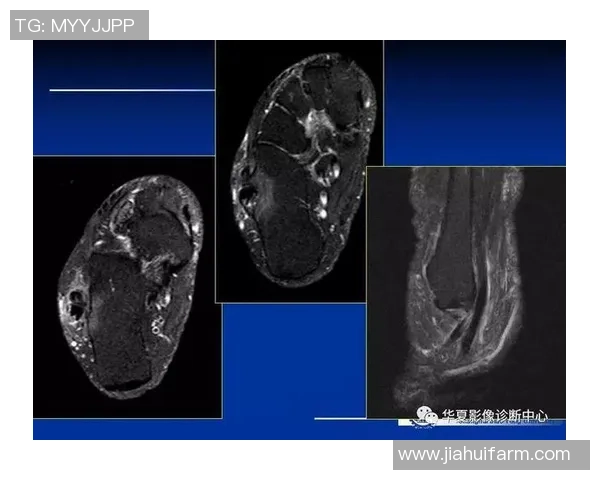

骨折则相对少见,但在高强度接触情况下可能会发生。这通常是由于直接撞击或扭转造成的,尤其是在比赛中与其他球员碰撞时,更容易出现这种情况。骨折后的疼痛感明显,而且会伴随肿胀和活动受限。

此外,韧带撕裂也是一种较为严重的损伤类型。它往往需要长期康复,因为完全愈合需要时间,并且若处理不当可能导致反复受伤。因此,在了解这些损伤类型后,我们更能有效预防和应对相关问题。

中度至重度扭伤及韧带撕裂通常需要专业医疗干预。在医生诊断后,可能会建议使用石膏或支架固定受影响区域,以促进愈合。同时,根据具体情况,还需进行物理治疗,通过专业手法来增强周围肌肉力量,提高关节稳定性。

对于骨折患者,则可能需要手术干预以修复骨头,并随后进行康复训练。在整个治疗过程中,与医生保持良好的沟通至关重要,这样才能确保恢复路径符合个人实际状况。